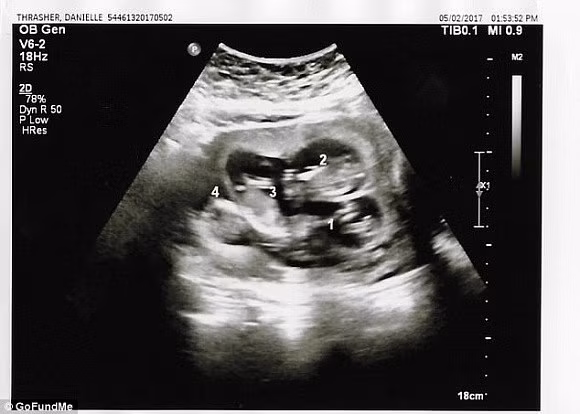

Thế nhưng, tuần thai thứ 13, trong một lần siêu âm, chị nhận được kết luận của bác sĩ rằng trong bụng chị đang có tới 4 bào thai đang phát triển. Thay vì ngỡ ngàng như lần trước, Joseph đã rất điềm tĩnh để chấp nhận chuyện này. Chồng chị Danielle nói: “Mặc dù chấp nhận điều này đồng nghĩa với việc hai đứa đã chuẩn bị tinh thần cho một cuộc sống có nhiều khó khăn về kinh tế phía trước nhưng chúng tôi sẽ cố gắng vì gia đình nhỏ của mình”.

Lần siêu âm thứ 3 thì các bác sĩ mới phát hiện ra em bé thứ tư.

Bác sĩ khám cho Danielle giải thích lý do tại sao đến lần siêu âm thứ ba mới phát hiện mang thai 4: “Bào thai thứ tư bị che khuất bởi lỗ rốn của Danielle, điều đó khiến chúng tôi không thể nhìn thấy trong những lần siêu âm trước. Còn việc mọi người hỏi rằng tại sao không kiểm tra kĩ trong quá trình siêu âm thì chúng tôi cho rằng việc thai phụ có 3, 4 hay 5 con không nằm trong dự đoán của chúng tôi và chúng tôi không có bất cứ lý do nào để kiểm tra xem liệu thai phụ đang mang bao nhiêu thai, nhất lại là trong những trường hợp như thế này, vị trí nằm của đứa trẻ không khiến chúng tôi đặt bất cứ nghi vấn nào”.